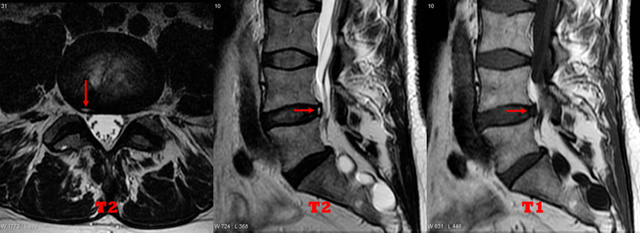

在L5-S1椎间盘的轴位图像上,纤维环中心可见T2高信号区。

下腰椎MRI显示L4/5椎间盘右后外侧环状裂。

其他意外发现包括硬膜外脂肪增多症和一些 Tarlov 囊肿。